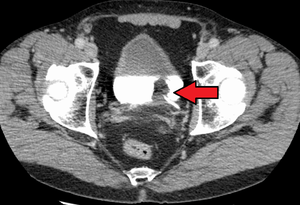

|

Transitional cell carcinoma of the bladder. The white in the bladder is contrast. | |